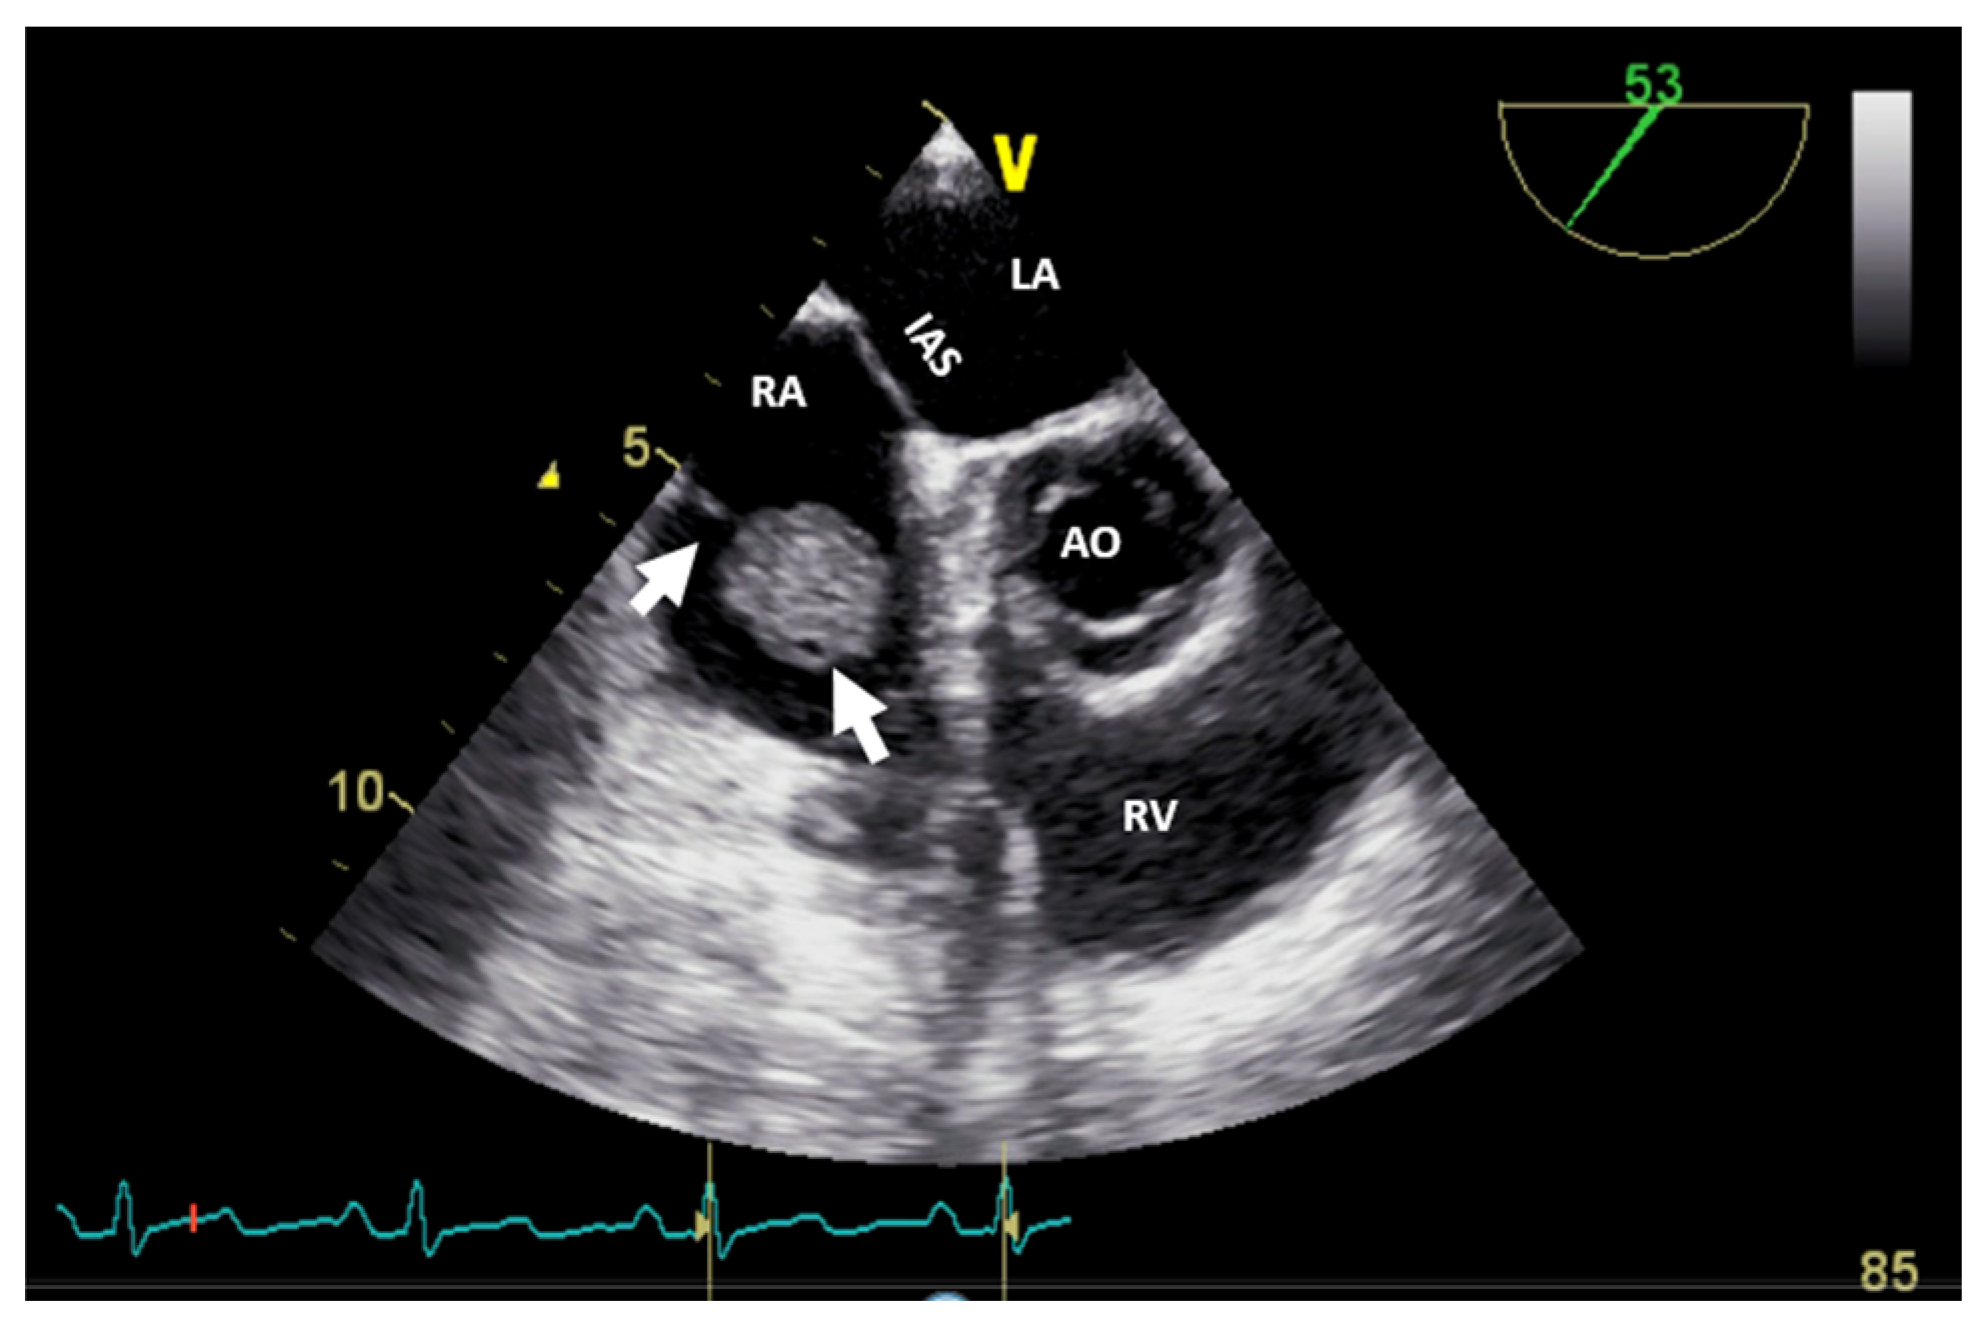

Figure 6.

Two-dimensional transesophageal echocardiography (short-axis view at the level of the great vessels) showing a mass (arrow) in the right atrium on the pacemaker leads. PM, pacemaker; RA, right atrium; RV, right ventricle; TV, tricuspid valve.

If the patient has a pacemaker or automatic implantable defibrillator, the first supposition in a clinical context suggestive of endocarditis is vegetation (Figure 6, Video S3—Supplementary Materials). A differential diagnosis must include fibrin formations or thrombi. However, if the patient is already anticoagulated (due to atrial fibrillation), these diagnoses are less likely.